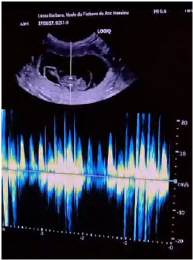

Wir waren am 10. April beim Ultraschall mit Neele, der hat uns Zuckersüsse Foeten mit gesundem Herzschlag 254 pro Minute gezeigt. Auch die Gebärmutter und alle Innereien sehen gesund aus.

Ultraschall-Video